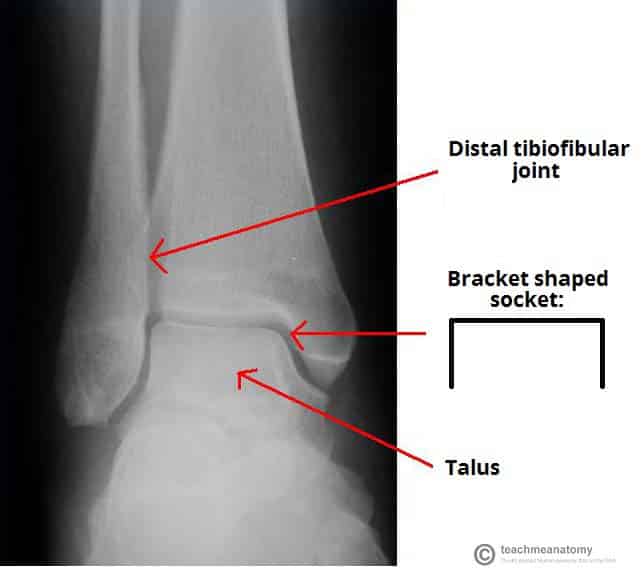

The ankle joint (or talocrural joint) is a synovial joint located in the lower limb. It is formed by the bones of the leg (tibia and fibula) and the foot (talus). Functionally, it is a hinge type joint, permitting dorsiflexion and plantarflexion of the foot. In this article, we shall look at the anatomy of the ankle joint; its articulating surfaces, ligaments, movements, and clinical correlations. By TeachMeSeries Ltd (2025) Fig 1The bones of the ankle joint; tibia, fibula and talus. Note that the calcaneous is not considered part of the ankle joint. Pro Feature - 3D Model You've Discovered a Pro Feature Access our 3D Model Library Explore, cut, dissect, annotate and manipulate our 3D models to visualise anatomy in a dynamic, interactive way. Learn More Articulating Surfaces The ankle joint is formed by three bones; the tibia and fibula of the leg, and the talus of the foot: The tibia and fibula are bound together by strong tibiofibular ligaments. Together, they form a bracket shaped socket, covered in hyaline cartilage. This socket is known as a mortise. The body of the talus fits snugly into the mortise formed by the bones of the leg. The articulating part of the talus is wedge shaped – it is broad anteriorly, and narrow posteriorly: Dorsiflexion – the anterior part of the talus is held in the mortise, and the joint is more stable. Plantarflexion – the posterior part of the talus is held in the mortise, and the joint is less stable. By TeachMeSeries Ltd (2025) Fig 2X-ray of a normal ankle joint. Note the bracket shaped socket formed by the tibia and fibula. By TeachMeSeries Ltd (2025) Fig 3The talus. It is broad anteriorly, which strengthens the joint during dorsiflexion. Ligaments There are two main sets of ligaments, which originate from each malleolus. Medial Ligament The medial ligament (or deltoid ligament) is attached to the medial malleolus (a bony prominence projecting from the medial aspect of the distal tibia). It consists of four ligaments, which fan out from the malleolus, attaching to the talus, calcaneus and navicular bones. The primary action of the medial ligament is to resist over-eversion of the foot. Lateral Ligament The lateral ligament originates from the lateral malleolus (a bony prominence projecting from the lateral aspect of the distal fibula). It resists over-inversion of the foot, and is comprised of three distinct and separate ligaments: Anterior talofibular – spans between the lateral malleolus and lateral aspect of the talus. Posterior talofibular – spans between the lateral malleolus and the posterior aspect of the talus. Calcaneofibular – spans between the lateral malleolus and the calcaneus. By OpenStax College [CC BY 3.0], via Wikimedia Commons Fig 4Ligaments of the ankle joint. Clinical Relevance The Ankle ‘Ring’ The ankle joint and associated ligaments can be visualised as a ring in the coronal plane: The upper part of the ring is formed by the articular surfaces of the tibia and fibula. The lower part of the ring is formed by the subtalar joint (between the talus and the calcaneus). The sides of the ring are formed by the medial and lateral ligaments. A ring, when broken, usually breaks in two places (the best way of illustrating this is with a polo mint – it is very difficult to break one side without breaking the other). When dealing with an injury to the ankle joint, a clinician must bear this in mind. For example, a fracture of the ankle joint may occur in association with ligament damage (which would not be apparent on x-ray). Movements and Muscles Involved The ankle joint is a hinge type joint, with movement permitted in one plane. Thus, plantarflexion and dorsiflexion are the main movements that occur at the ankle joint. Eversion and inversion are produced at the other joints of the foot, such as the subtalar joint. Plantarflexion – produced by the muscles in the posterior compartment of the leg (gastrocnemius, soleus, plantaris and posterior tibialis). Dorsiflexion – produced by the muscles in the anterior compartment of the leg (tibialis anterior, extensor hallucis longus and extensor digitorum longus). Neurovascular Supply The arterial supply to the ankle joint is derived from the malleolar branches of the anterior tibial, posterior tibial and fibular arteries. Innervation is provided by tibial, superficial fibular and deep fibular nerves. Clinical Relevance Ankle Sprain An ankle sprain refers to partial or complete tears in the ligaments of the ankle joint. It usually occurs via excessive inversion to a plantarflexed and weight-bearing foot. The lateral ligament is more likely to be damaged for two main reasons: The lateral ligament is weaker than the medial ligament. The lateral ligament resists inversion. The anterior talofibular ligament is the lateral ligament most at risk of irreversible damage. Clinical Relevance Pott’s Fracture-Dislocation A Pott’s fracture is a term used to describe a bimalleolar (medial and lateral malleoli) or trimalleolar (medial and lateral malleoli, and distal tibia) fracture. This type of injury is produced by forced eversion of the foot. It occurs in a series of stages: Forced eversion pulls on the medial ligaments, producing an avulsion fracture of the medial malleolus. The talus moves laterally, breaking off the lateral malleolus. The tibia is then forced anteriorly, shearing off the distal and posterior part against the talus. By Steven Fruitsmaak [CC BY-SA 3.0], from Wikimedia Commons Fig 5Bimalleolar fracture of the ankle. 1 – Fibula, 2 – Tibia. Do you think you’re ready? Take the quiz below Pro Feature - Quiz The Ankle Joint Question 1 of 3 Submitting... Skip Next Rate question: You scored 0% Skipped: 0/3 1800 More Questions Available Upgrade to TeachMeAnatomy Pro Challenge yourself with over 1800 multiple-choice questions to reinforce learning Learn More Rate This Article